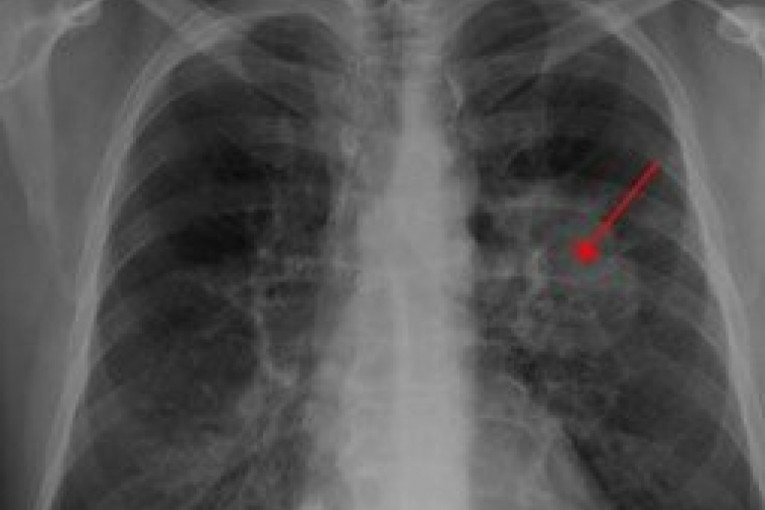

Većina ljudi sa rakom pluća nema simptome dok bolest ne uznapreduje. Nažalost, u nekim slučajevima spasa nema. Jednoj ženi iz Nju Džersija, koja je otišla u Hitnu pomoć sa bolom u ramenu, dijagnostikovan je rak pluća koji se proširio na druge delove njenog tela i umrla je 25 dana kasnije.

Uradili su joj CT sken i biopsiju kostiju koji su otkrili da ima rak po nazivu adenokarcinom, koji se javio u dnu levog plućnog krila, a koji se proširio na kičmu, rebra i nadbubrežnu žlezdu. Iako se rak nije proširio na rame, u kom je osećala bol, lekari veruju da ga je uzrokovaka jedne od kanceroznih lezija na kičmi. Ova pacijentkinja je nekada pušila, ali ne u toj meri da bi ispunila kriterijume za skrining raka pluća. Ona je pušila jednu paklu dnevno otprilike pet godina, zbog čega su lekari smatrali da je mala verovatnoća da je ova loša navika uticala na razvoj kancera.